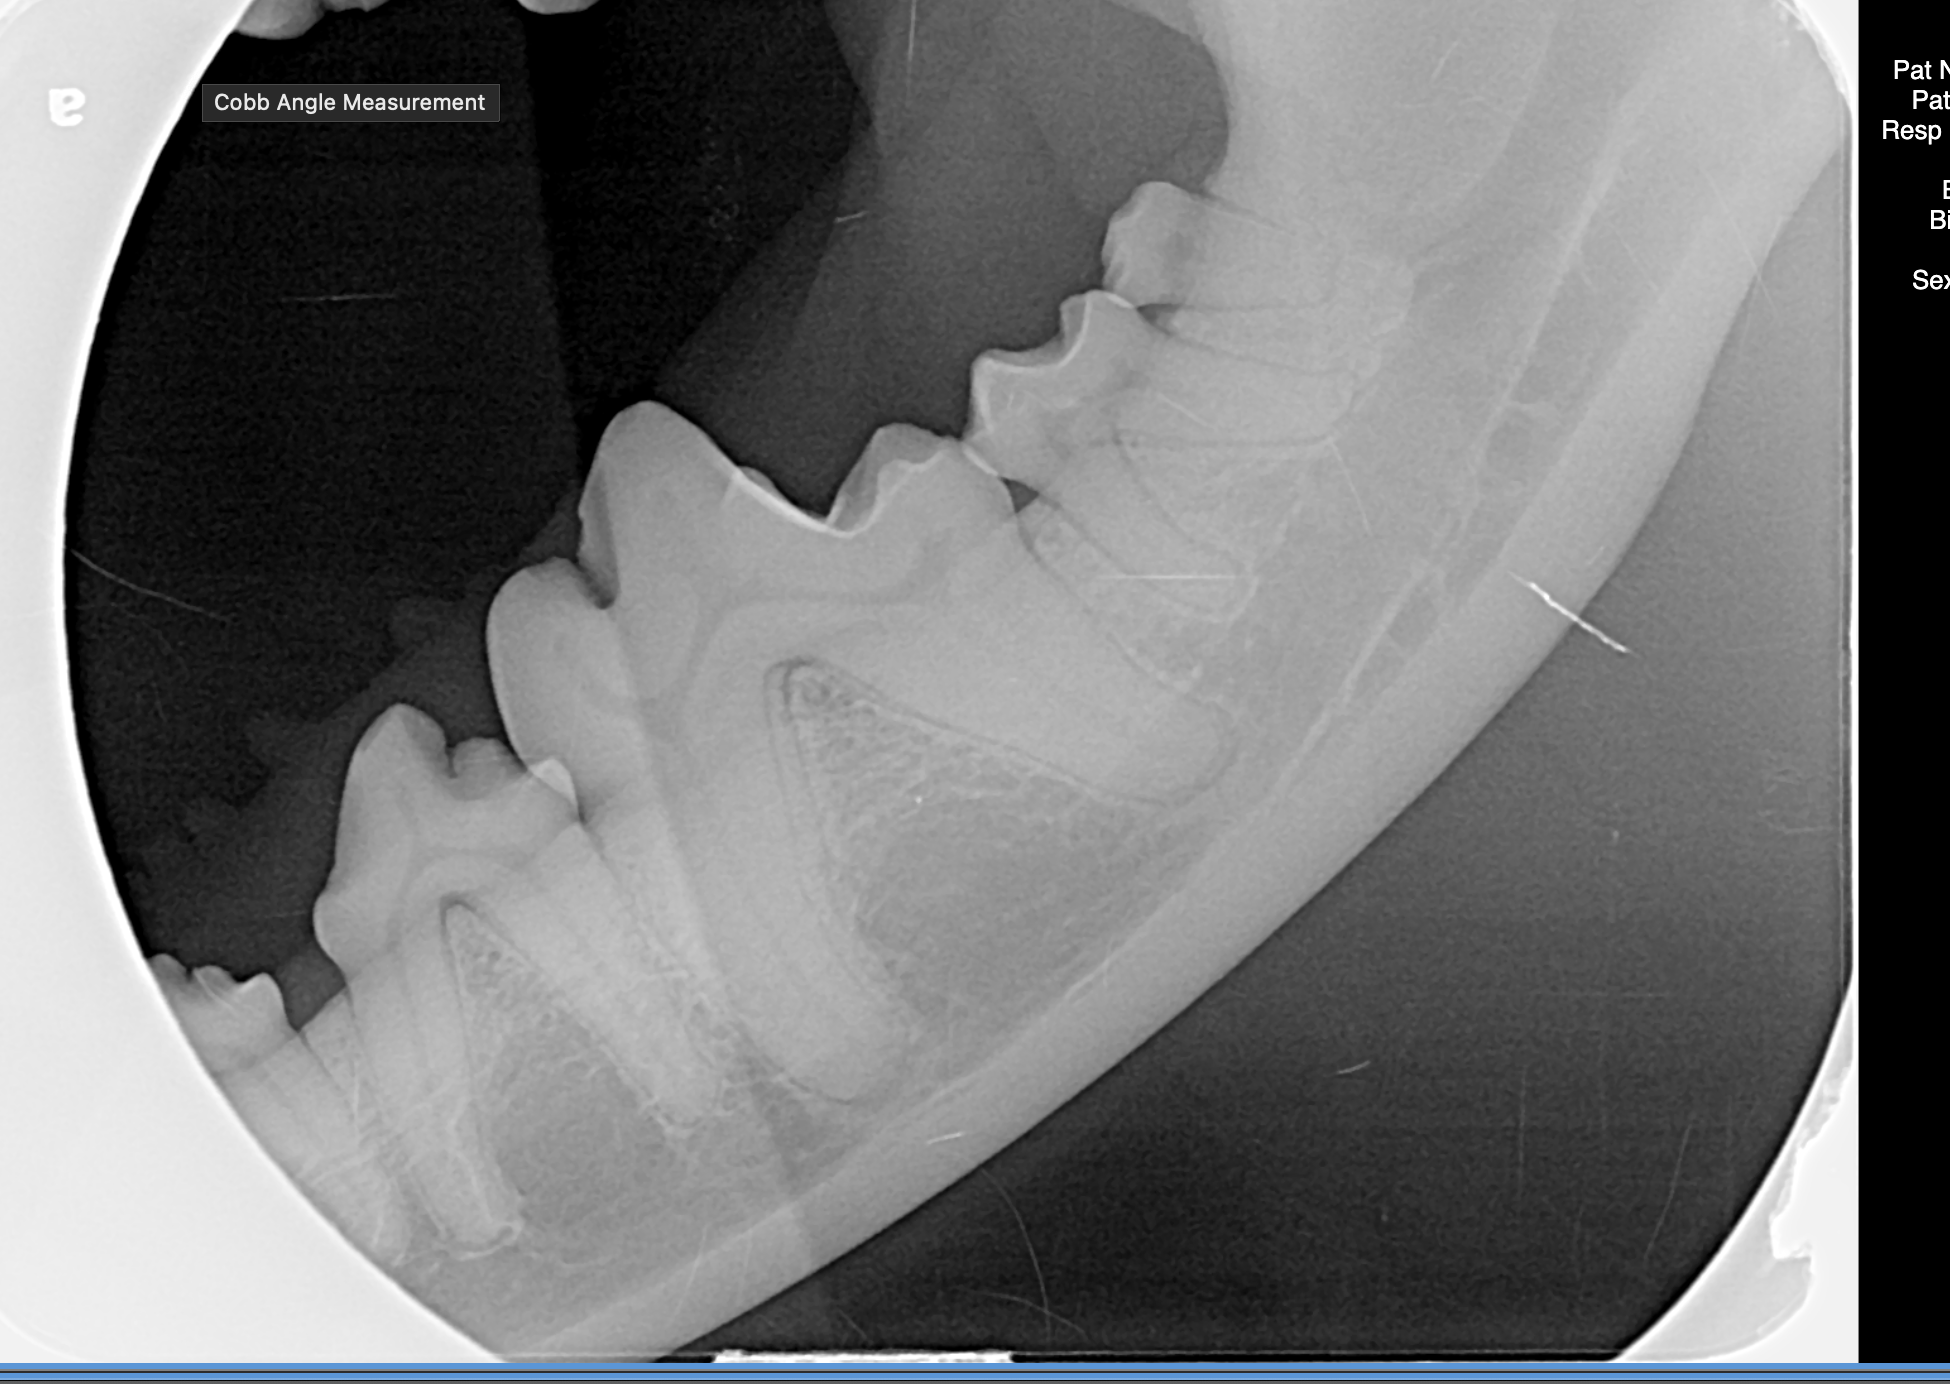

Advanced Diagnostics

Ontario's first Veterinary Dental Hospital featuring Cone-Beam CT,  Dental Radiology, in-house laboratory and more.